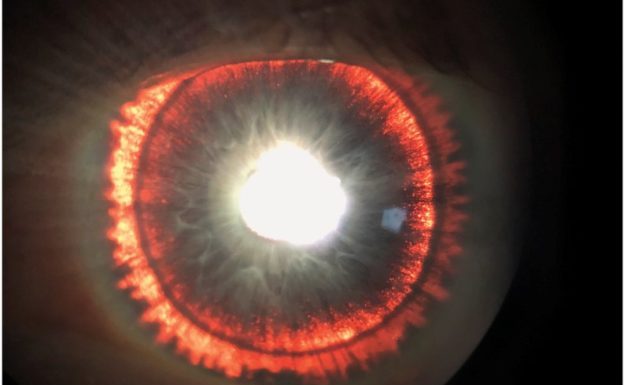

美國一名男子的眼睛宛如火焰燃燒般的「索倫之眼」,這不是因為他被黑暗魔君附身,也不是決定要征服中土世界,而是罹患了罕見的色素擴散症候群(Pigment dispersion syndrome)。